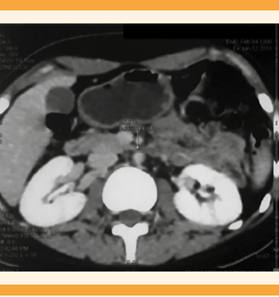

Paciente de 21 años, sin antecedentes familiares de importancia, originaria y residente de Piedras Negras, Coahuila, de ocupación estudiante. Grupo y Rh O+. Antecedente de linfoma de Hodgkin tipo nodular escleroso, EC IIA Bulky, diagnosticado en 2016 y tratada con 8 ciclos de quimioterapia (clorhidrato de doxorrubicina, sulfato de bleomicina, sulfato de vinblastina y dacarbazina) y 20 sesiones de radioterapia, la última en febrero del 2018. Como parte del seguimiento se le practicó una tomografía por emisión de positrones multicorte, sin evidencia de actividad tumoral. El hallazgo radiológico fue de concentración del radiofármaco de manera circunferencial en la aorta, en todo su trayecto, con SUVmax de 2.0, asociado con placas ateromatosas mixtas (Figura 1). Además, engrosamiento circunferencial de la íntima, de localización infrarrenal, que condicionó la disminución de la luz mayor de 95%, antes de su bifurcación (Figuras 2y3). Se trató con ácido acetilsalicílico y pravastatina.

Figura 2 Engrosamiento circunferencial de la íntima de la aorta abdominal infrarrenal. (Flecha con punta blanca).